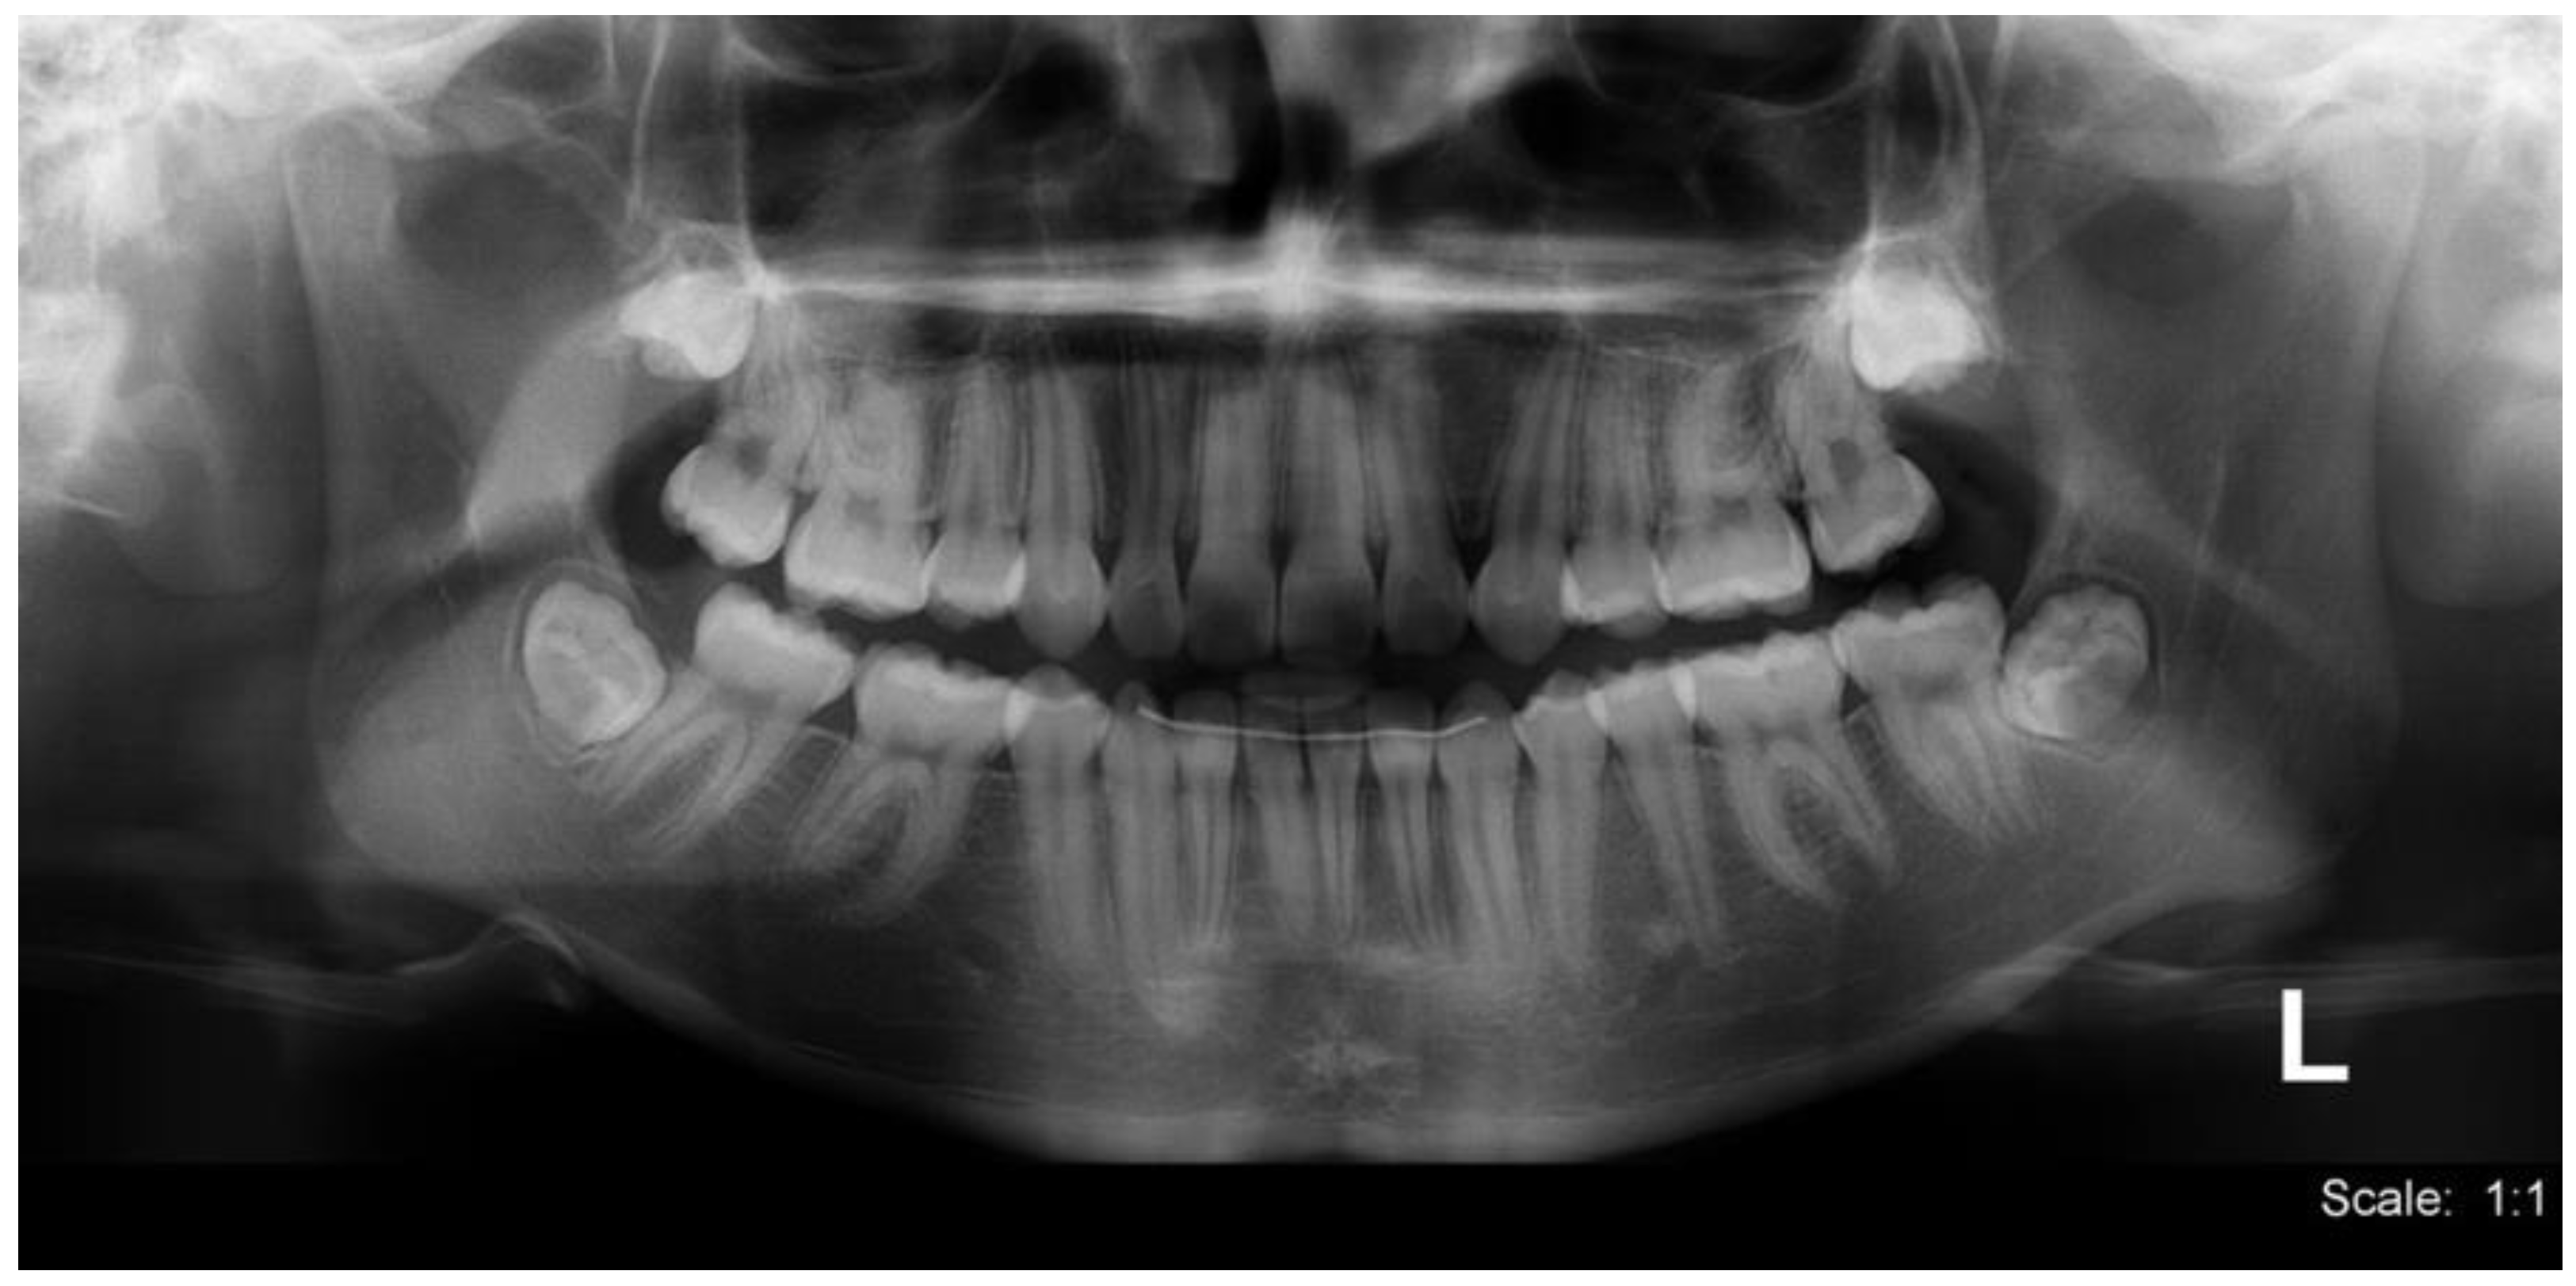

2. Case Report